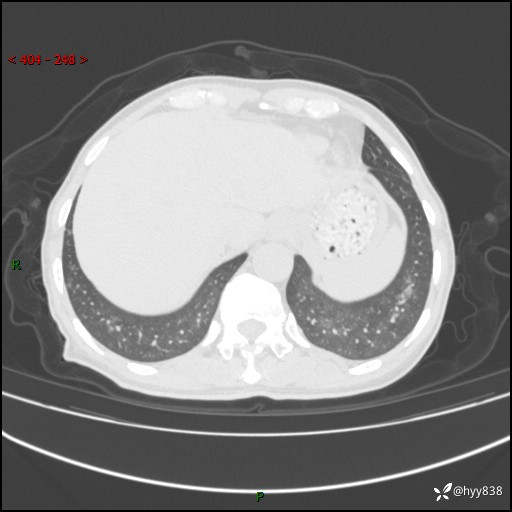

辅助检查:CT

胸部CT平扫

不是讨论肺部结节